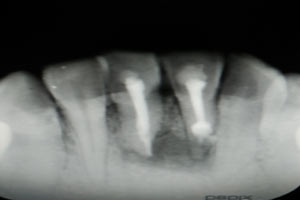

圖2.術(shù)前的根尖片影像、31根管治療已做,欠填少許。31、41根尖有橢圓形陰影,未見明顯骨白線。

圖3.術(shù)中x線片檢查:31預(yù)備植根中1/3與根尖1/3遇阻力,根管測量無法測到長度,根尖1/3牙膠無法取出。

圖6.根管治療+樹脂充填后根尖片影像:31根尖1/3大量根充物溢出。因此必須同期根管外科治療

圖18.術(shù)后的根尖片影像檢查: